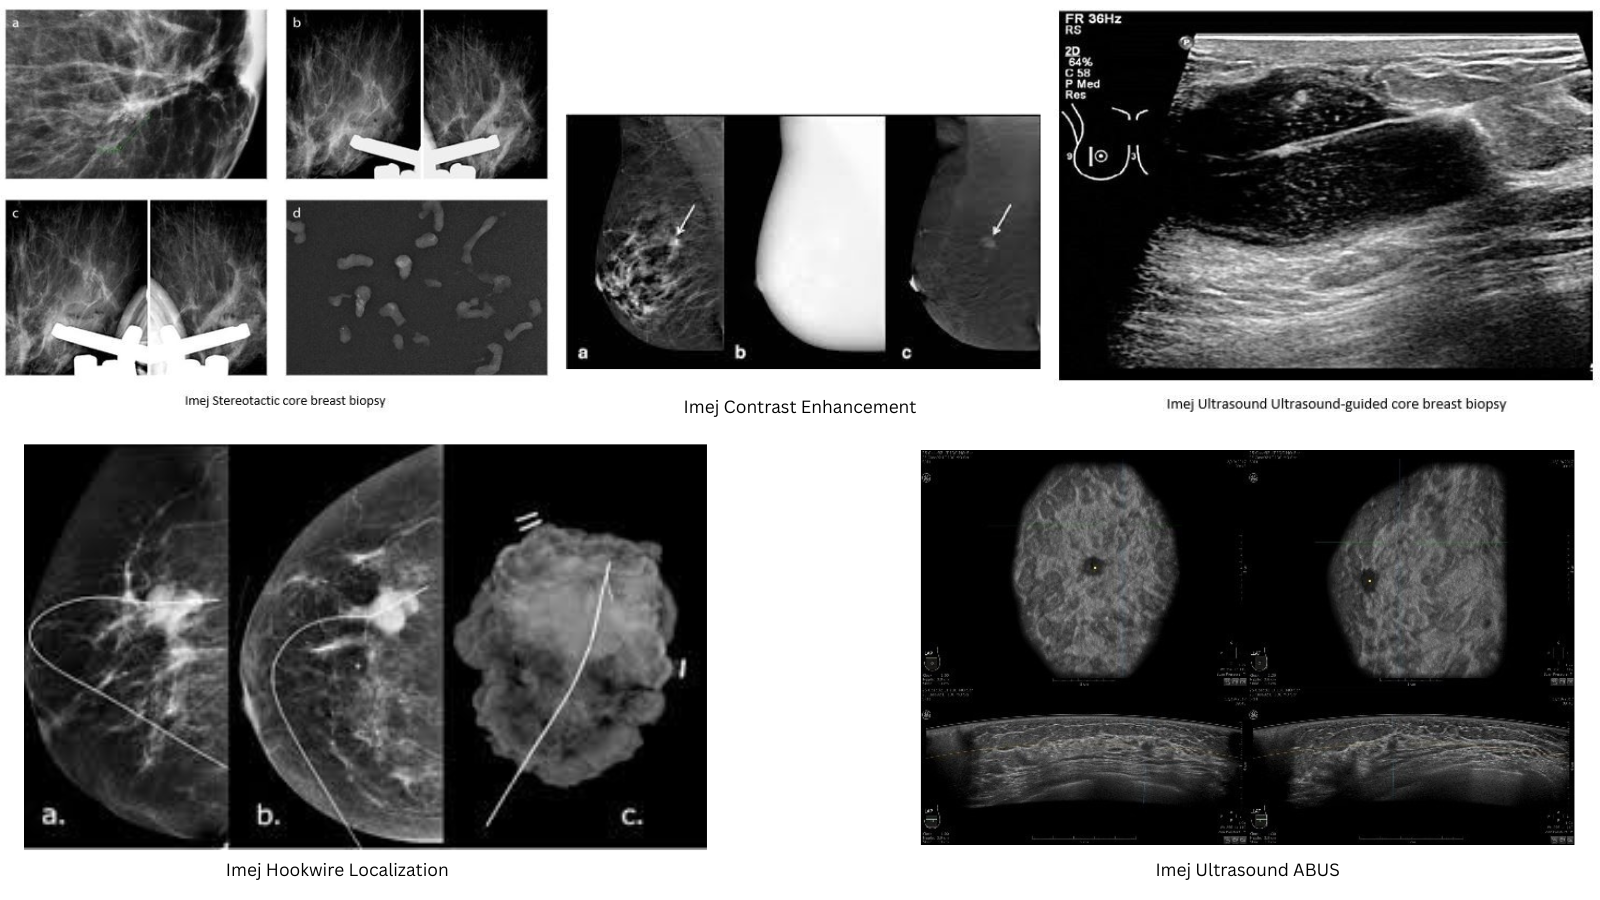

• Stereotactic Core Breast Biopsy

• CESM-Contrast Enhancement Spectral Mammography

• Ultrasound 2D dan 3D

• Ultrasound-guided abscess aspiration

• Ultrasound-guided breast core biopsy

• Ultrasound-Guided Hookwire Localization